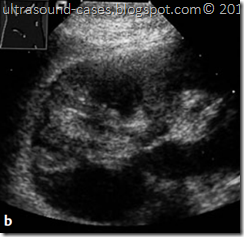

ultrasound images Renal Infarctiona, b Renal infarction. a Wedge-shaped, s harply circumscribed hyperechoic area. b Magnification: The triangular avascular area confirms the infarction. The patient presented clinically with flank pain. For CDS see also Figs.

x The kidney may appear sonographically normal in the acute stage of a renal

artery embolism, or it may contain a wedge-shaped hypoechoic area whose

apex points toward the renal pelvis.

x Later an echogenic triangular scar develops, causing an indentation of the renal

surface with narrowing of the parenchymal border.